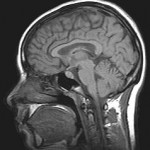

Interestingly, different types of meditation incite different anatomical changes in the brain, but all have some similar effects. This is yet another example of self-directed neuroplasticity — the effect of thought on the brain.

One type of meditation emphasizes “loving-kindness” and compassion towards others. A practitioner gets away from ordinary concerns and worries, and then concentrates on love and compassion. The brain imaging of this type of meditation showed an increase of activity in the frontal part of the brain, linked with positive emotions and self-control, and in the thalamus,

which regulates and filters sensory and motor signals for the higher cortical centers. Moreover, activity is decreased in the parietal region, associated with visual and spatial information. Finally, the electroencephalograph (EEG), which measures electrical activity of the brain, showed increased activity in frequency ranges related to concentration.

Another type of meditation is mindfulness, which involves the release of bodily and sensory attachment by focusing on the present. Practitioners of this meditation shift their attention to their breath, their heartbeat, their inner thoughts, or an object. After a while, meditators have physical increases in the number of neurons and

neuronal connections in sections of their cortex. Those sections are: the right frontal cortex, related to concentration; the right insula, related to emotions; and the right parietal and temporal lobes related to touch and sound. A recent study also showed that after eight weeks brain imaging showed reduction in the volume of the amygdala, related to anxiety and stress, and an increase in the number of neurons in the hippocampus, related to learning and memory.

A third type of meditation, called ‘Transcendental Meditation,” has the mind play a specific sound in the background which is chosen from the ancient tradition of meditation. At first the sound buzzes in the mental background like a song stuck in our head. Gradually, this breaks attachments to other thoughts and experiences. In this type of meditation, the frontal and parietal regions, associated with attention, grow more active.

On the other hand, regions of the thalamus, related to sensory input, and basal ganglion, to choosing behaviors and actions show decreased activity. Finally, the EEG readings show that many brain regions have increased coherence. That is, brainwaves tend to be more “in phase,” passing through the brain in a more rhythmic and orderly manner.

A very recent study of a variety of meditation techniques showed increased connectivity in the areas related to memory, learning and emotion, including centers in cortex, spinal cord, and cerebellum.

Another further significant recent study showed that with all of the techniques mentioned there is increased folding of the cortex, that is increased “gyrification.” Increased gyrus formation is thought to increase processing of information. Also significant in this study is that the longer people had practiced the various forms of meditation, the more this effect of increased cortical surface area was noted.